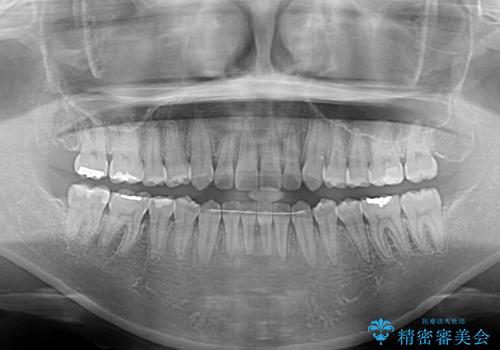

カリエールディスタライザーを併用したことで、すっきりとした口元になり、上下の正中を合わせることができました。